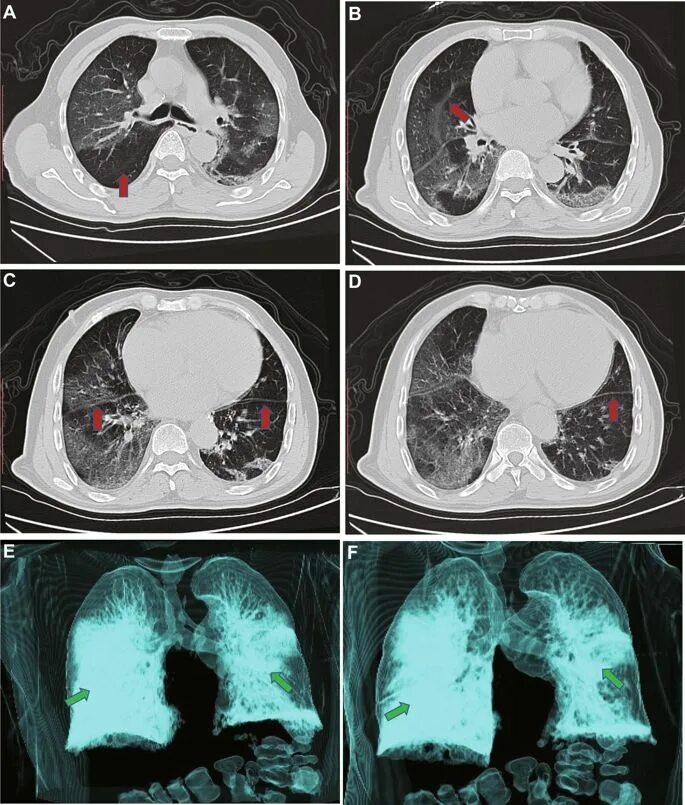

Болит кт